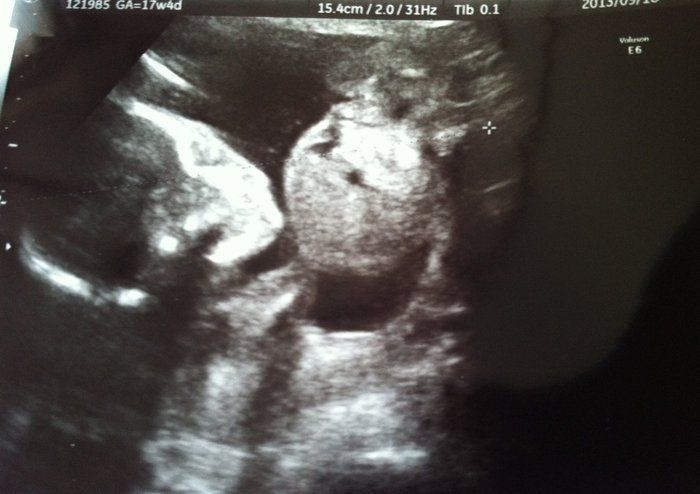

Tomomiさんの妊娠17週目のエコー写真 性別判明!!ママはルンルン、パパは少し残念そう!?

この日のベビちゃんはお股を大開脚したり、こちらにお顔を向けて口をもごもごしたりと、大サービスしてくれました。先生からの「どっちか知りたい?」のお言葉に、食い付き気味に「ハイ!」と答える私。念願の女の子と分かり、「一緒にお料理したり、買い物行ったりしたいな」と、気が早すぎる妄想を膨らませていました。パパは「一緒にキャッチボールがしたい」なんて言っていたので少し残念そうだったけれど、元気な我が子のエコー写真にニヤニヤでした。